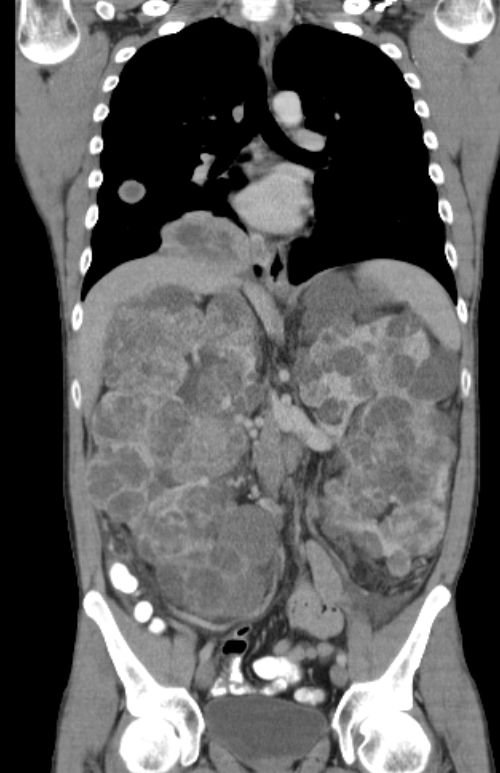

Riesige Zystennieren beiderseits.

Die Zystennieren enthielter beiderseits Nierenzellkarzinome. Die Lungenmetastasierung ist erkennbar.